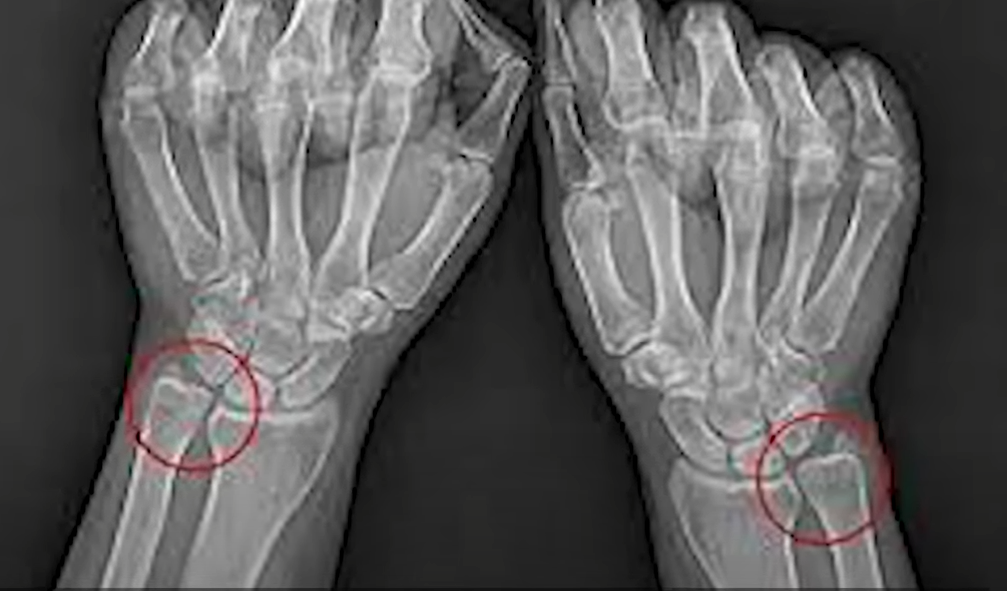

이렇게 되면 손목이 뒤로 기울면서 거기에 더해 바깥쪽으로 뻗히게 되고 이런 운동 습관이 지속되면 척골과 삼각 연골이 서로 어긋난 각도로 꺾이게 되면서 퇴화 혹은 염증이 일어나게 되죠.

손은 손목 관절 하나가 아닌 정말 다양한 뼈의 분절 종합체이기 때문에 이런 식으로 무게를 손으로 박게 되면 삼각연골 주변부에 정말 쉽게 과부하가 걸리게 됩니다.

아는 분들은 많으시겠지만, 아래 손바닥 부위로 잡게 되면 척골과 삼각연골이 정렬을 이루면서 안정적으로 중량이 받쳐지게 됩니다.

다시 말해, 엄지와 검지로 쥐어잡는 부분을 통해 요골의 지지을 만들어내고 바깥쪽 손바닥 부위에 비스듬히 파지 해 주면 척골의 지지를 만들어낼 수 있습니다.

요골과 척골이 무게를 균등하게 지탱하면서 손목에 부담은 사실상 없어지는 원리죠.